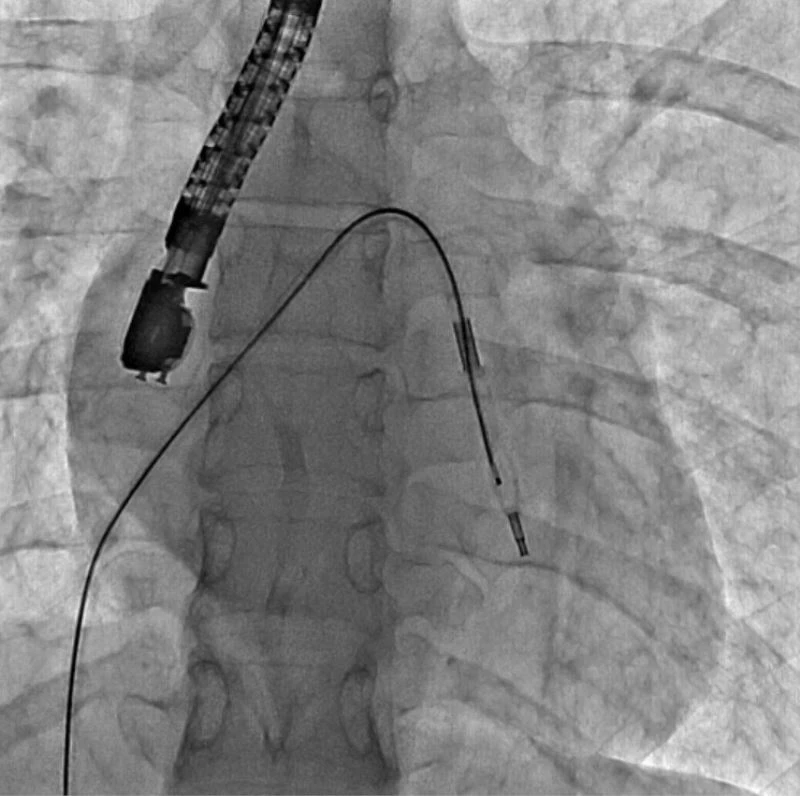

Eskişehir Şehir Hastanesi’nde ilk defa mitral balon operasyonu yapıldı. Operasyon, anjiyografi cihazı ile adım adım kaydedildi.

Eskişehir Şehir Hastanesi’nde Kardiyoloji Uzmanı Dr. Mehmet Özgeyik ve 4 kişilik ekibi tarafından ilk defa mitral balon operasyonu yapıldı. Türkiye’de az sayıda yapılan kalp kapağı balon işlemiyle yeni anne olmuş genç bir hasta sağlığına kavuştu. Bu sayede hastalar ameliyat olmaktan, ömür boyu kan sulandırıcı ilaçlar kullanmaktan ve metal bir kalp kapağı ile yaşamaktan kurtuluyor.

Gerçekleşen başarılı operasyon hakkında konuşan Kardiyoloji Uzmanı Dr. Mehmet Özgeyik, "Bu işlemi genellikle kalp kapaklarında ciddi darlık olan genç hastaların kişilere uyguluyoruz. Buradaki amacımız ameliyat olmadan, kasıktan küçük iki damar yolu açarak hastalarımızın kapak darlıklarını uzun süreli olarak genişletmeyi hedefliyoruz. Burada 23 yaşında yeni anne olmuş genç bir hastamıza müdahale yaptık. Hastamız ya kapak ameliyatı olacaktı ya da bu işlem sayesinde kapak darlığını aşmayı planlıyorduk. İşlem gayet başarılı oldu. Hastamızın kapak darlığını genişlettik. En azından 10-15 sene boyunca ameliyata gerek kalmadan hastamızı ilaç tedavisiyle takip etmeyi planlıyoruz" diye konuştu.

Cerrahi operasyonlar yerine mitral balon işlemiyle hastaları sağlıklarına kavuşturmak istediklerini aktaran Dr. Özgeyik, "Hastanemizde ilk kez yapılan bir işlem. Bu işlem için uygun hasta bulmak biraz zor oluyor çünkü çok sık yapılan bir işlem değil. Fakat gelecekte hasta portföyümüzün de artması ile birlikte daha sık yapmayı planlıyoruz. En azından hastalarımızı büyük bir cerrahi operasyona vermeden böyle küçük işlemlerle hayat kalitelerini artırmayı planlıyoruz. Hastamız ameliyata gitmiş olsaydı büyük bir operasyon geçirmiş olacaktı. Göğüs bölgesinde büyük bir kesiğe maruz kalacaktı. Aynı zamanda ömür boyu kullanması gereken farklı ilaçlar olacaktı. Hasta kendisine ait olmayan metal bir kapakla yaşamak zorunda kalacaktı. Biz bu işlemde hastaya kasıktan iki tane damar yolu açtık. Hastaya neşter ile kesme işlemi uygulamaktan kurtardık. Ayrıca hastanın hayatı boyunca kullanacağı kan sulandırıcı ilaçları uzunca bir süre ertelemiş olduk. En önemlisi de hastanın kendi kalp kapağını kullanmasını sağlamış olduk ve metal kapak yükünden kurtulmuş oldu" şeklinde konuştu.